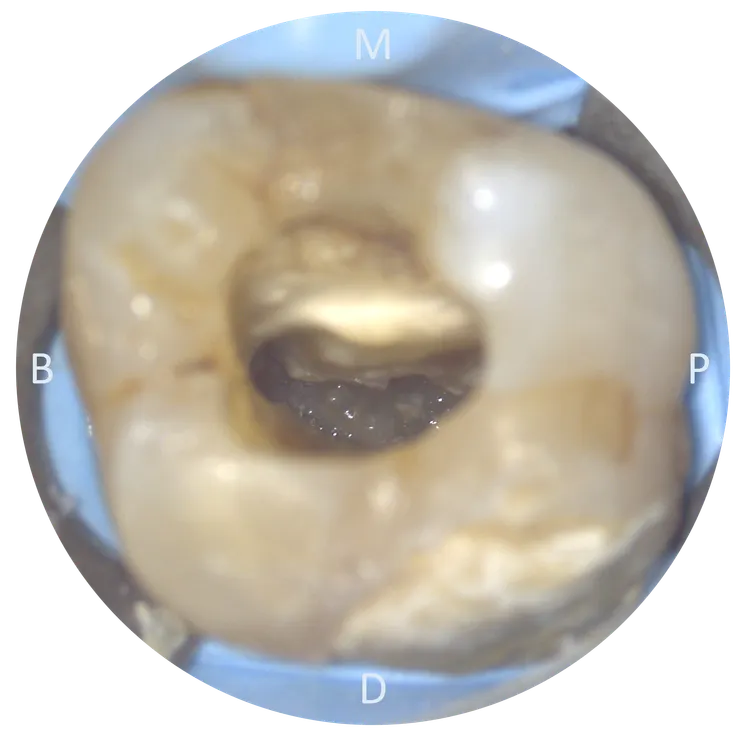

這是顆經過 prepare, fresh 的牙。

找到 chamber 後,先修形出理想的 outline form,讓 wall 在保留足夠厚度的同時,chamber 內也不要留下太多 undercut.

完成初步的 access cavity 後,可以看到 mesial wall 有非常突出的 dentin shelf 蓋住底下的 chamber floor.

車掉那片 dentin shelf 後,露出了 chamber floor.

此時隱約可以看到 P, DB, MB orifices.

繼續把 mesial wall 的 undercut 修掉, MB2 orifice 就顯露出來了。